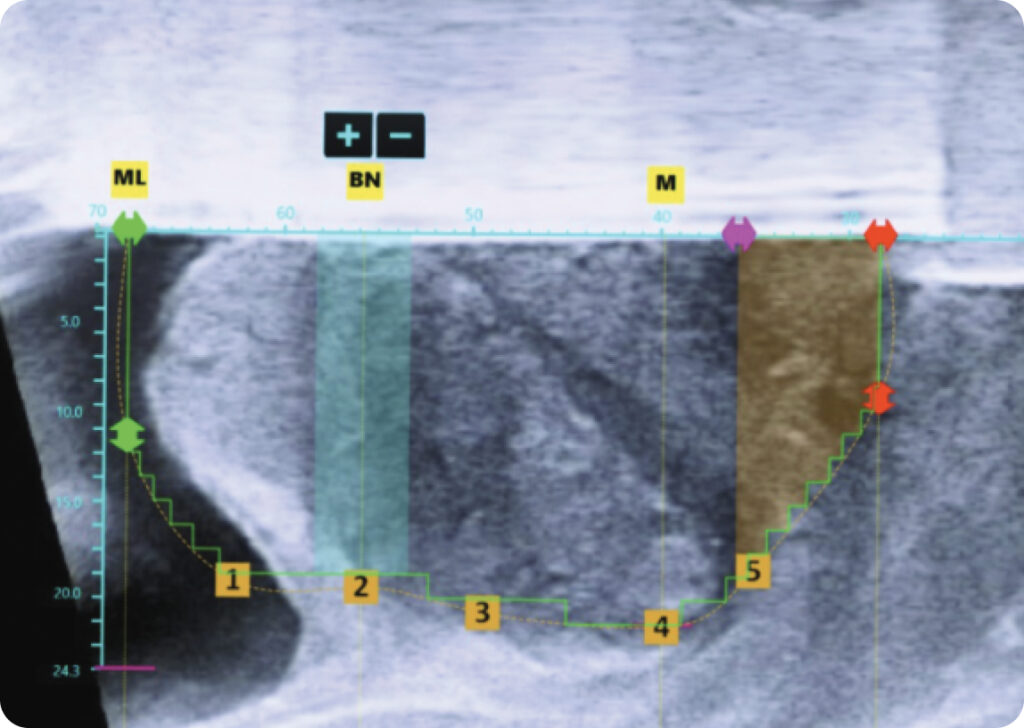

Personalized Treatment Planning

Computer-assisted planning allows the surgeon to maximize tissue resection while sparing the bladder neck, verumontanum, and external sphincter.